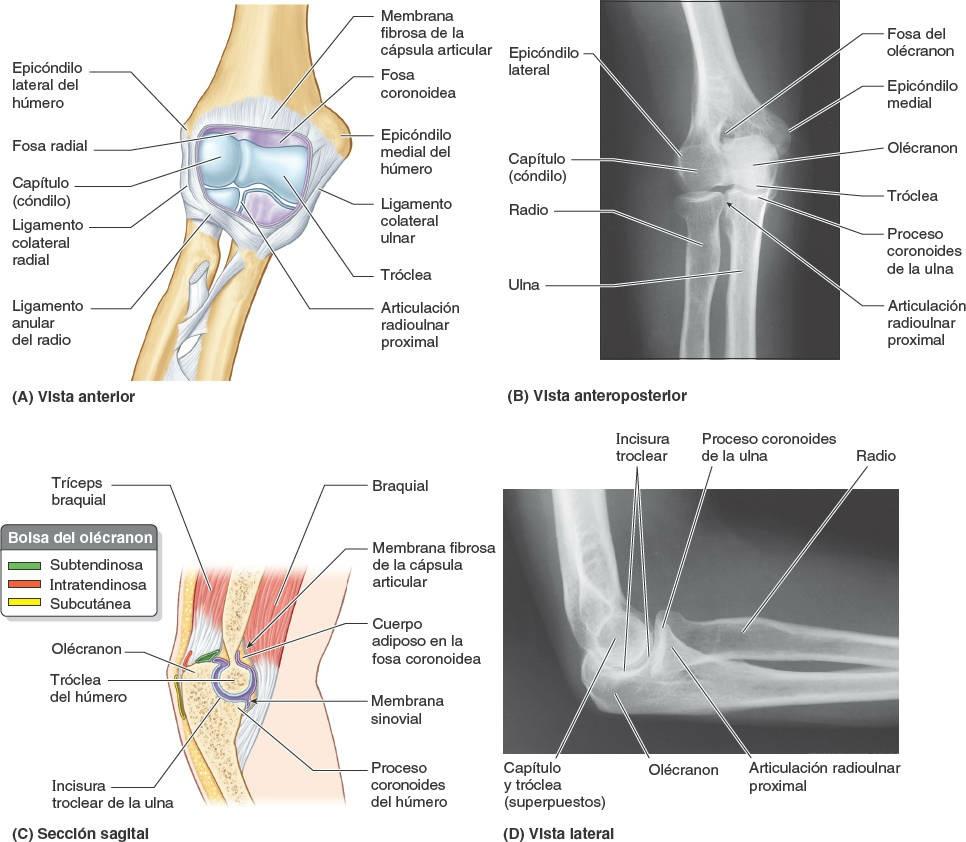

La articulación del codo es una articulación sinovial de tipo gínglimo que se localiza 2-3 cm por debajo de los epicóndilos del húmero (fig. 3-97).

La tróclea en forma de polea y el capítulo (cóndilo) esferoideo del húmero se articulan con la incisura troclear de la ulna y la cara superior ligeramente cóncava de la cabeza del radio, respectivamente; en consecuencia, existe una articulación humeroulnar y una humerorradial. Las superficies articulares, recubiertas de cartílago hialino, son casi completamente congruentes (se encuentran en contacto) cuando el antebrazo se sitúa en una posición a medio camino entre la pronación y la supinación, y el codo está flexionado en ángulo recto.

Cápsula articular

La membrana fibrosa de la cápsula articular rodea la articulación del codo (fig. 3-97 A y C). Se inserta en el húmero en los bordes de los extremos lateral y medial de las superficies articulares del capítulo y la tróclea. Anterior y posteriormente se dirige en sentido ascendente hasta situarse proximal a las fosas coronoidea y del olécranon.

La membrana sinovial recubre la superficie interna de la membrana fibrosa de la cápsula y las partes intracapsulares no articulares del húmero. Inferiormente también se continúa con la membrana sinovial de la articulación radioulnar proximal. La cápsula articular es débil anterior y posteriormente, pero está reforzada en cada lado por ligamentos colaterales.

Ligamentos

Los ligamentos colaterales de la articulación del codo son potentes bandas triangulares formadas por engrosamientos laterales y mediales de la membrana fibrosa de la cápsula articular (figs. 3-97 A y 3-98). El ligamento colateral radia, lateral y en forma de abanico, se extiende desde el epicóndilo lateral del húmero para fusionarse distalmente con el ligamento anular del radio, que rodea y sujeta la cabeza del radio en la incisura radial de la ulna para que se forme la articulación radioulnar proximal y se pueda pronar y supinar el antebrazo.

El ligamento colateral ulnar, medial y triangular, se extiende desde el epicóndilo medial del húmero hasta el proceso coronoides y el olécranon de la ulna, y consta de tres fascículos:

- fascículo anterior, similar a un cordón, que es el más potente;

- fascículo posterior, en forma de abanico, que es el más débil, y

- fascículo oblicuo, delgado, que hace más profunda la cavidad para la tróclea del húmero.

Bolsas en torno a la articulación del codo

Sólo algunas de las bolsas que rodean la articulación del codo son clínicamente importantes. Las tres bolsas del olécranon (figs. 3-97 C y 3-101) son:

- La bolsa intratendinosa del olécranon, que en ocasiones se encuentra en el tendón del tríceps braquial.

- La bolsa subtendinosa (del músculo tríceps braquial del olécranon), que se localiza entre el olécranon y el tendón del tríceps, justo proximalmente a su inserción en el olécranon.

- La bolsa subcutánea del olécranon, que se localiza en el tejido conectivo subcutáneo situado por encima del olécranon.

Articulación radioulnar proximal

La articulación radioulnar proximal (superior) es una articulación sinovial de tipo trocoide que permite el movimiento de la cabeza del radio sobre la ulna (figs. 3-97 A, B y D, y 3-102).